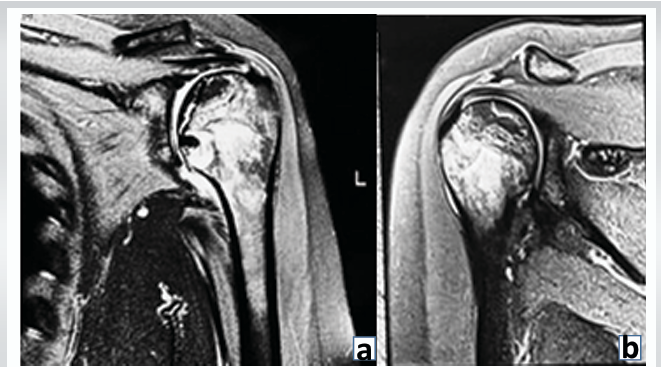

A 27-year-old female presented with chief complaints of pain and swelling in her right ankle for 8 months and in her left shoulder for 4 months. The pain started spontaneously and was gradually progressive. The patient had no history of trauma. Two years before the onset of symptoms, the patient had a history of GBS for which the patient took intravenous (IV) immunoglobulins for 4 days, IV steroids for 1 week, followed by oral steroids for 3 months. Examination of all individual joints was done under suspicion of MSON and revealed tenderness in both shoulders with limited internal rotation on the left (four vertebral levels down). Both hips showed joint line tenderness with painful terminal degrees of range of motion (ROM). The right knee had lateral joint line tenderness and painful terminal degrees of flexion, while the left knee was clinically normal. The right ankle had anterior joint line tenderness and painful terminal dorsiflexion; the left ankle was normal. Radiological studies showed ON of both humeral heads (Cruess stage – 2 [7]) with greater involvement on the left side (Fig. 1a and b).

Figure 1a & b: Pre-operative magnetic resonance imaging both shoulders. 1.5. T. Proton density (PD) fat saturation, coronal images showing irregular, serpiginous PD hyperintensities in proximal humerus, Left (a) > Right (b), humerus contour and joint space maintained. Suggestive of avascular necrosis of both humeral heads (Cruess-II).